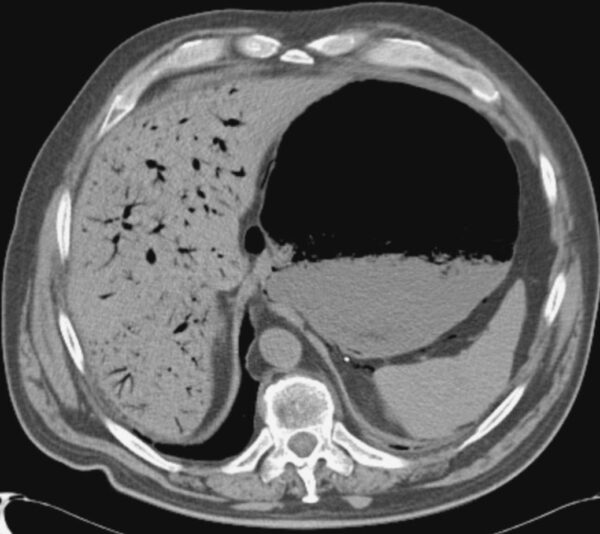

Case 35

https://radiopaedia.org/articles/portal-venous-gas

CT

GIT